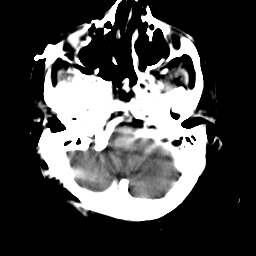

Meningioma: Roentgen-ray CT #1 -- Slice #1

[Home][Help][Clinical] Slice 1